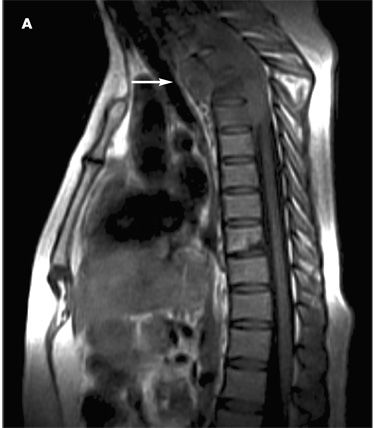

A 43-year-old woman had worsening thoracic and lumbar pain associated with tingling and tightness in the anterior upper and lower abdominal area. An urgent MRI of the thoracic spine showed a soft tissue mass that extended from C7 to T4 and involved the prevertebral, paravertebral, and intraspinal spaces (arrow); this caused compression and posterior displacement of the spinal cord and an anterior T2 vertebrae compression fracture.